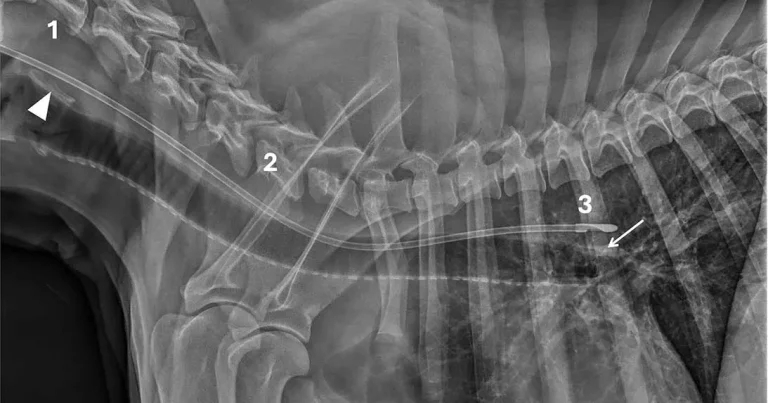

Figure 1. Case one.

To identify the landmarks in the radiographs in Figures 1-5, arrowheads indicate the lamina of cricoid cartilage of the larynx (when included), and arrows show the dorsal wall of the carina. Additionally, numbers highlight the three criteria and landmarks: (one) larynx, (two) tracheal lumen, and (three) carina.

Case one

This lateral cervical and thoracic radiograph (Figure 1) of a dog includes the larynx and shows:

- Dorsal passage of the tube at the level of the lamina of cricoid cartilage (arrowhead).

- Incomplete tracheal overlap.

- A position dorsal to the carina (arrow).

Laryngeal cartilages tend to mineralise in older dogs and occasionally in younger large-breed dogs, as in this case, with the lamina of cricoid cartilage typically the most apparent.

Interpretation. Correct oesophageal placement. All criteria were met, so the tube was safely positioned for feeding.